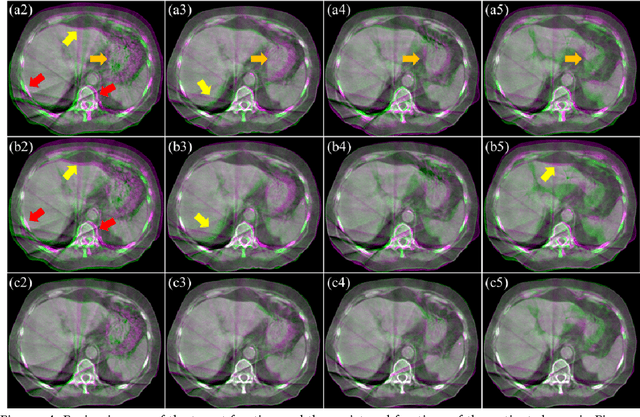

Abstract:CBCTs in image-guided radiotherapy provide crucial anatomy information for patient setup and plan evaluation. Longitudinal CBCT image registration could quantify the inter-fractional anatomic changes. The purpose of this study is to propose an unsupervised deep learning based CBCT-CBCT deformable image registration. The proposed deformable registration workflow consists of training and inference stages that share the same feed-forward path through a spatial transformation-based network (STN). The STN consists of a global generative adversarial network (GlobalGAN) and a local GAN (LocalGAN) to predict the coarse- and fine-scale motions, respectively. The network was trained by minimizing the image similarity loss and the deformable vector field (DVF) regularization loss without the supervision of ground truth DVFs. During the inference stage, patches of local DVF were predicted by the trained LocalGAN and fused to form a whole-image DVF. The local whole-image DVF was subsequently combined with the GlobalGAN generated DVF to obtain final DVF. The proposed method was evaluated using 100 fractional CBCTs from 20 abdominal cancer patients in the experiments and 105 fractional CBCTs from a cohort of 21 different abdominal cancer patients in a holdout test. Qualitatively, the registration results show great alignment between the deformed CBCT images and the target CBCT image. Quantitatively, the average target registration error (TRE) calculated on the fiducial markers and manually identified landmarks was 1.91+-1.11 mm. The average mean absolute error (MAE), normalized cross correlation (NCC) between the deformed CBCT and target CBCT were 33.42+-7.48 HU, 0.94+-0.04, respectively. This promising registration method could provide fast and accurate longitudinal CBCT alignment to facilitate inter-fractional anatomic changes analysis and prediction.